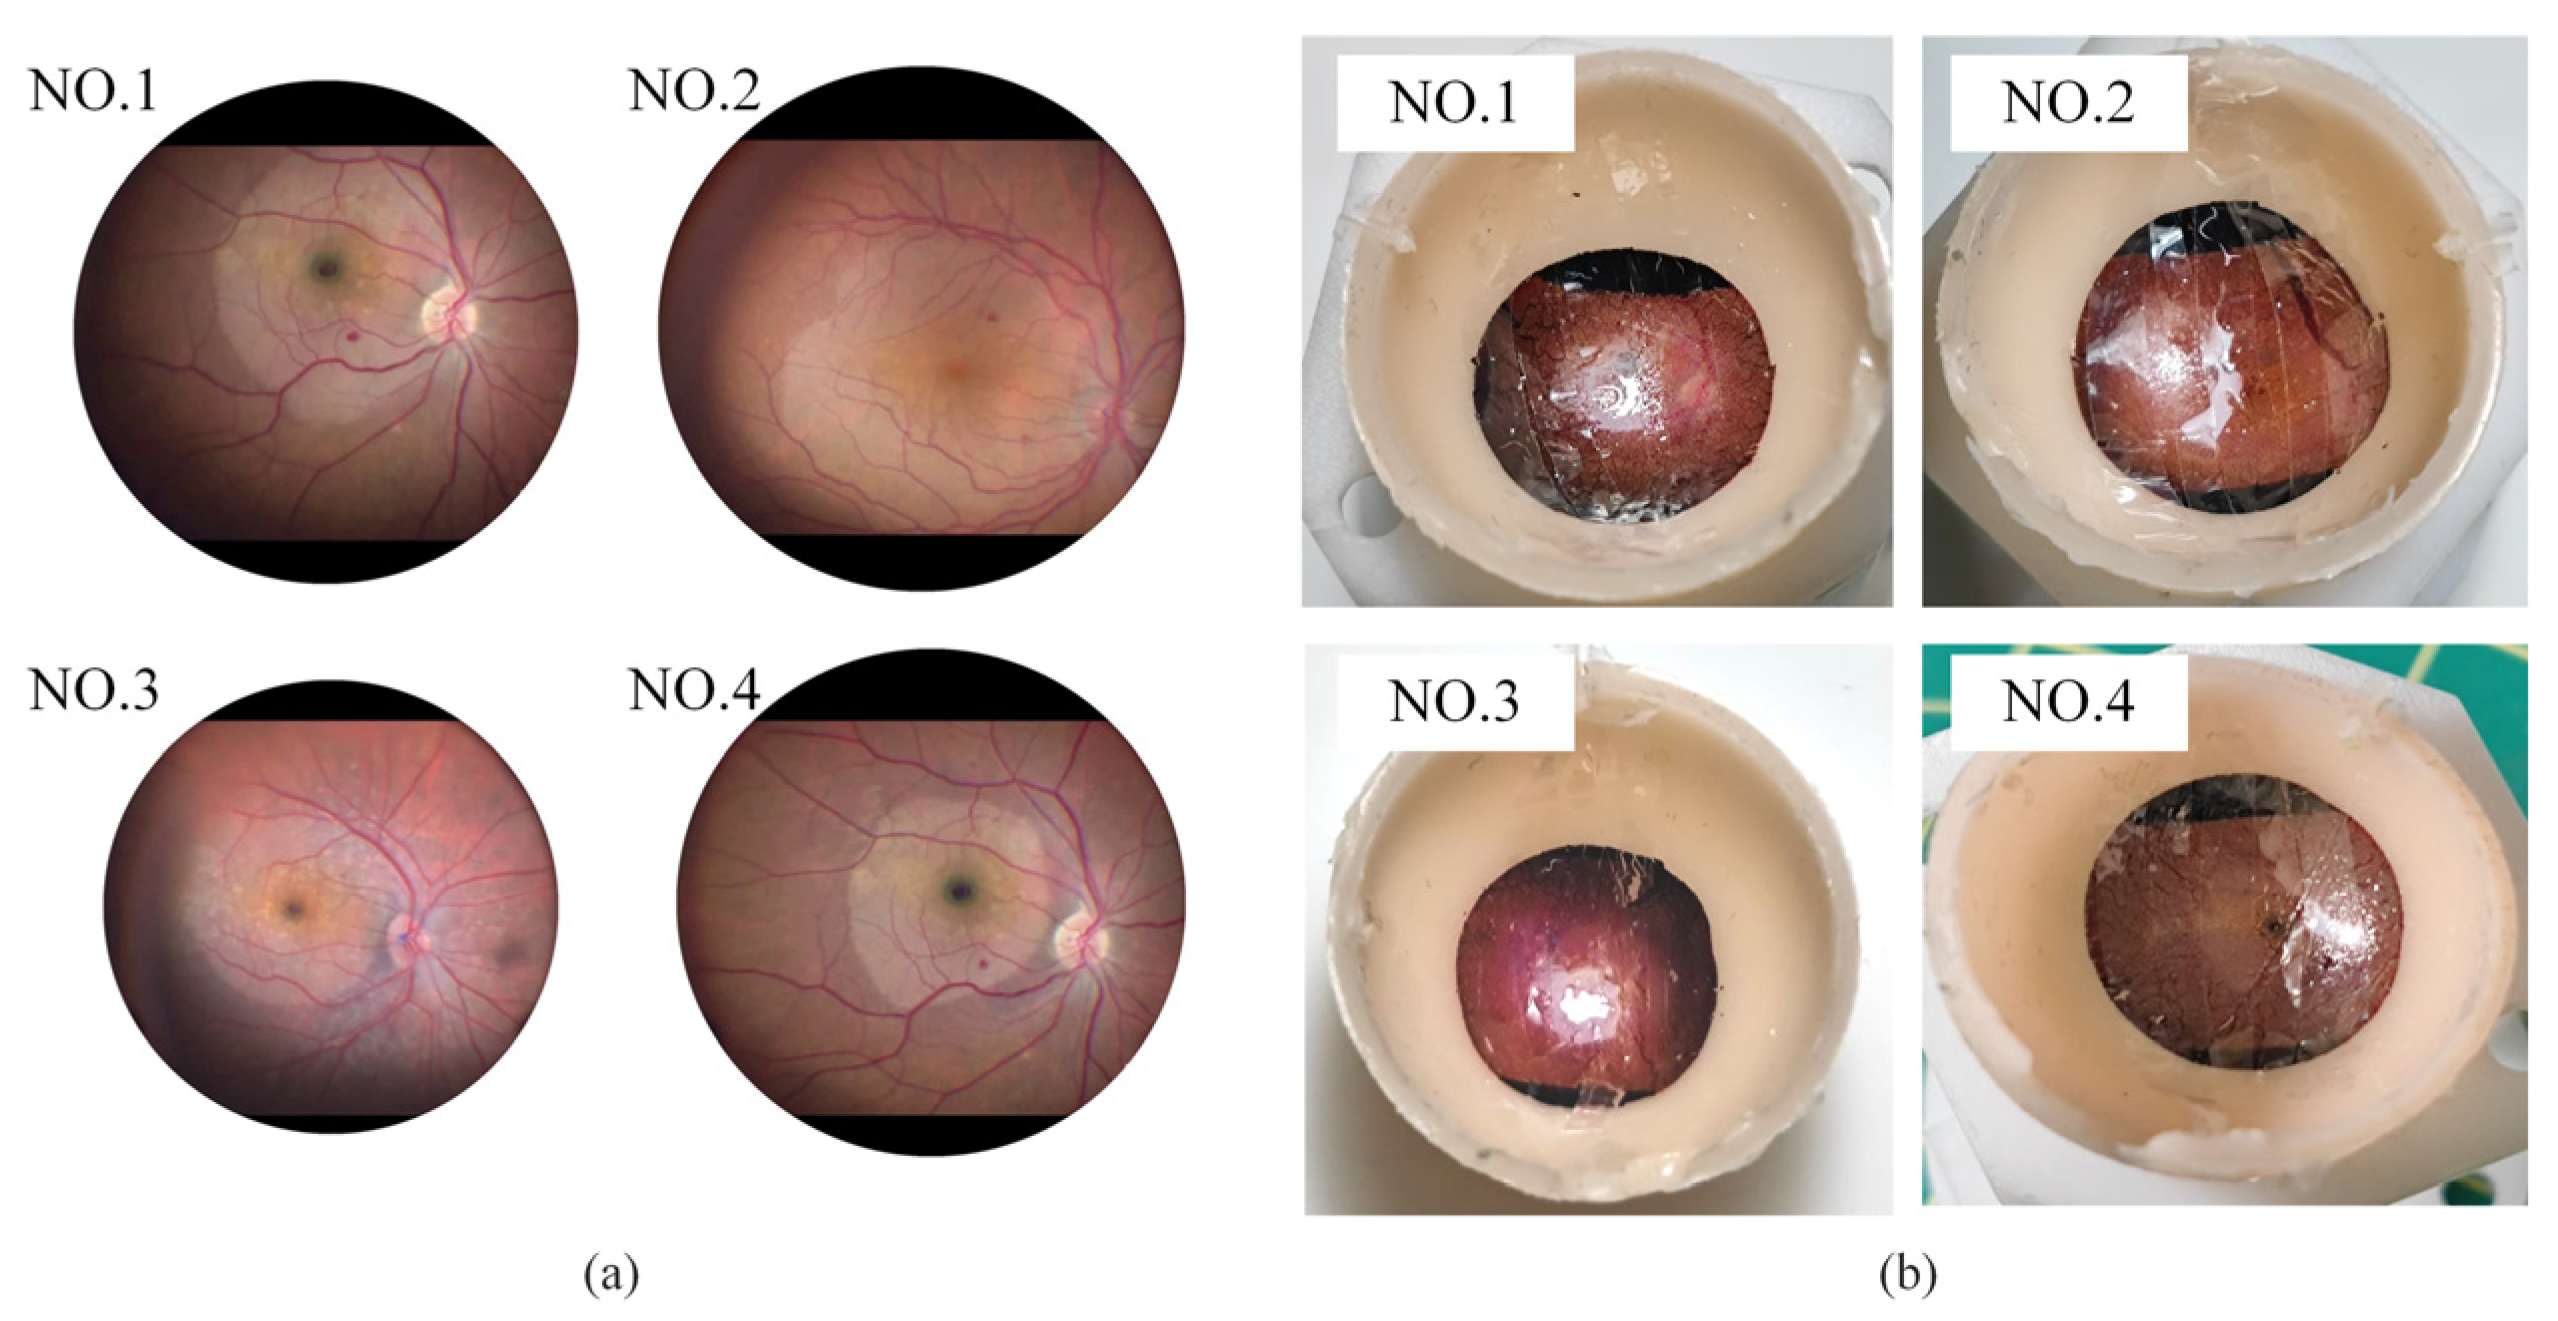

4.1. Experimental Setup

4.3. Break Initiation Experiment in ILM Peeling